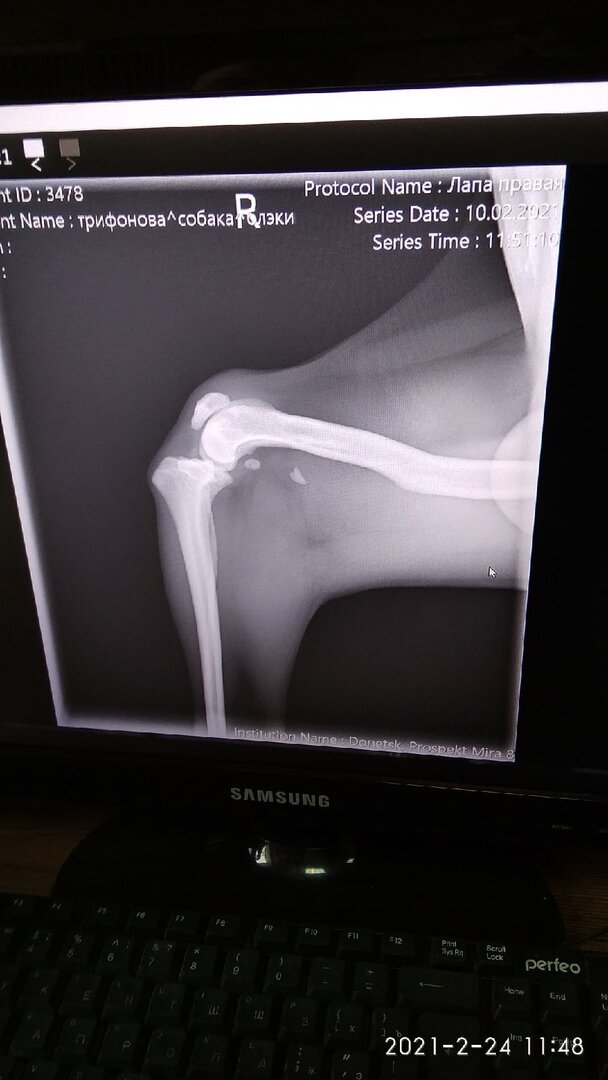

По лапе смотрели в Пифе сегодня, сказали делать уже нет смысла (( Да здесь и некому. Так что будет прихрамывать. Пёс Блэки: немного о планах с нашим мальчиком и жизни на передержке!)